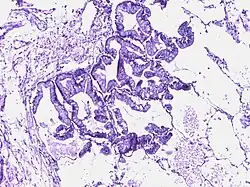

![]() | Bronchoalveolar carcinoma | Lepidic pattern of growth of tumor cells along the alveolar wall resembling butterfly sitting on fence. Normal alveoli is seen towards right side. | Category: Histopathology of bronchio-alveolar carcinoma | Bronchio-alveolar carcinoma |